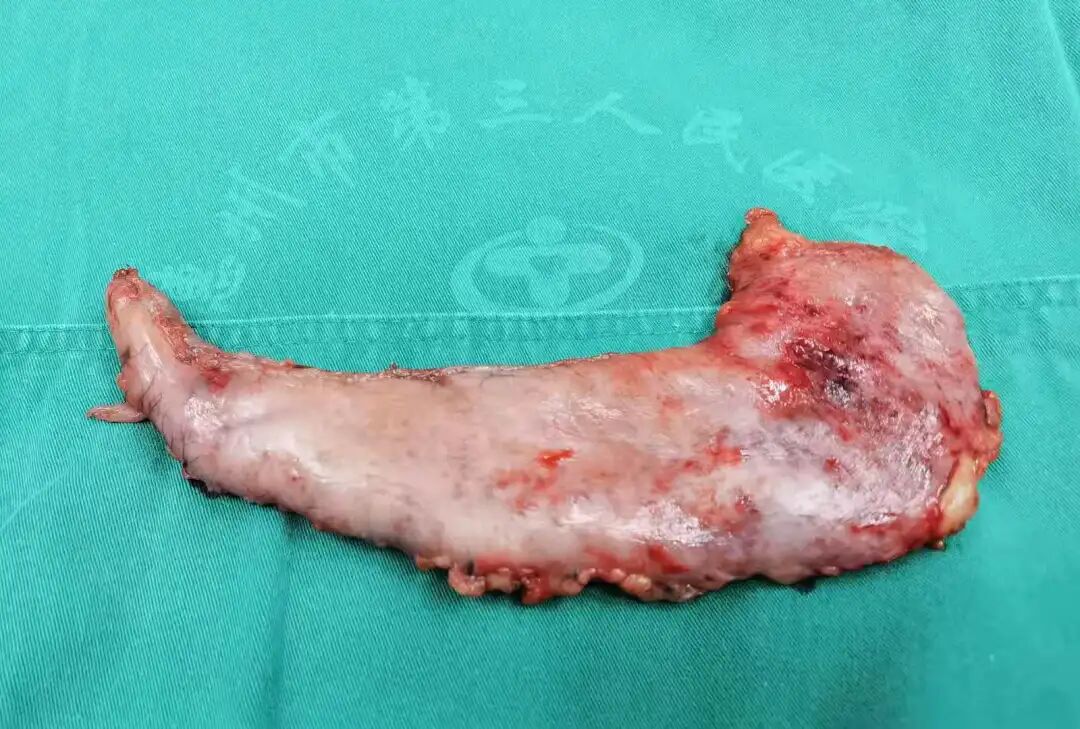

切除的胃組織

袖狀胃手術(shù)(LSC)通過(guò)切除胃底及大彎側(cè)的大部分胃組織,切除量約80%,剩余容積在60-100ml,使殘留的胃呈“香蕉”樣的管狀通道。